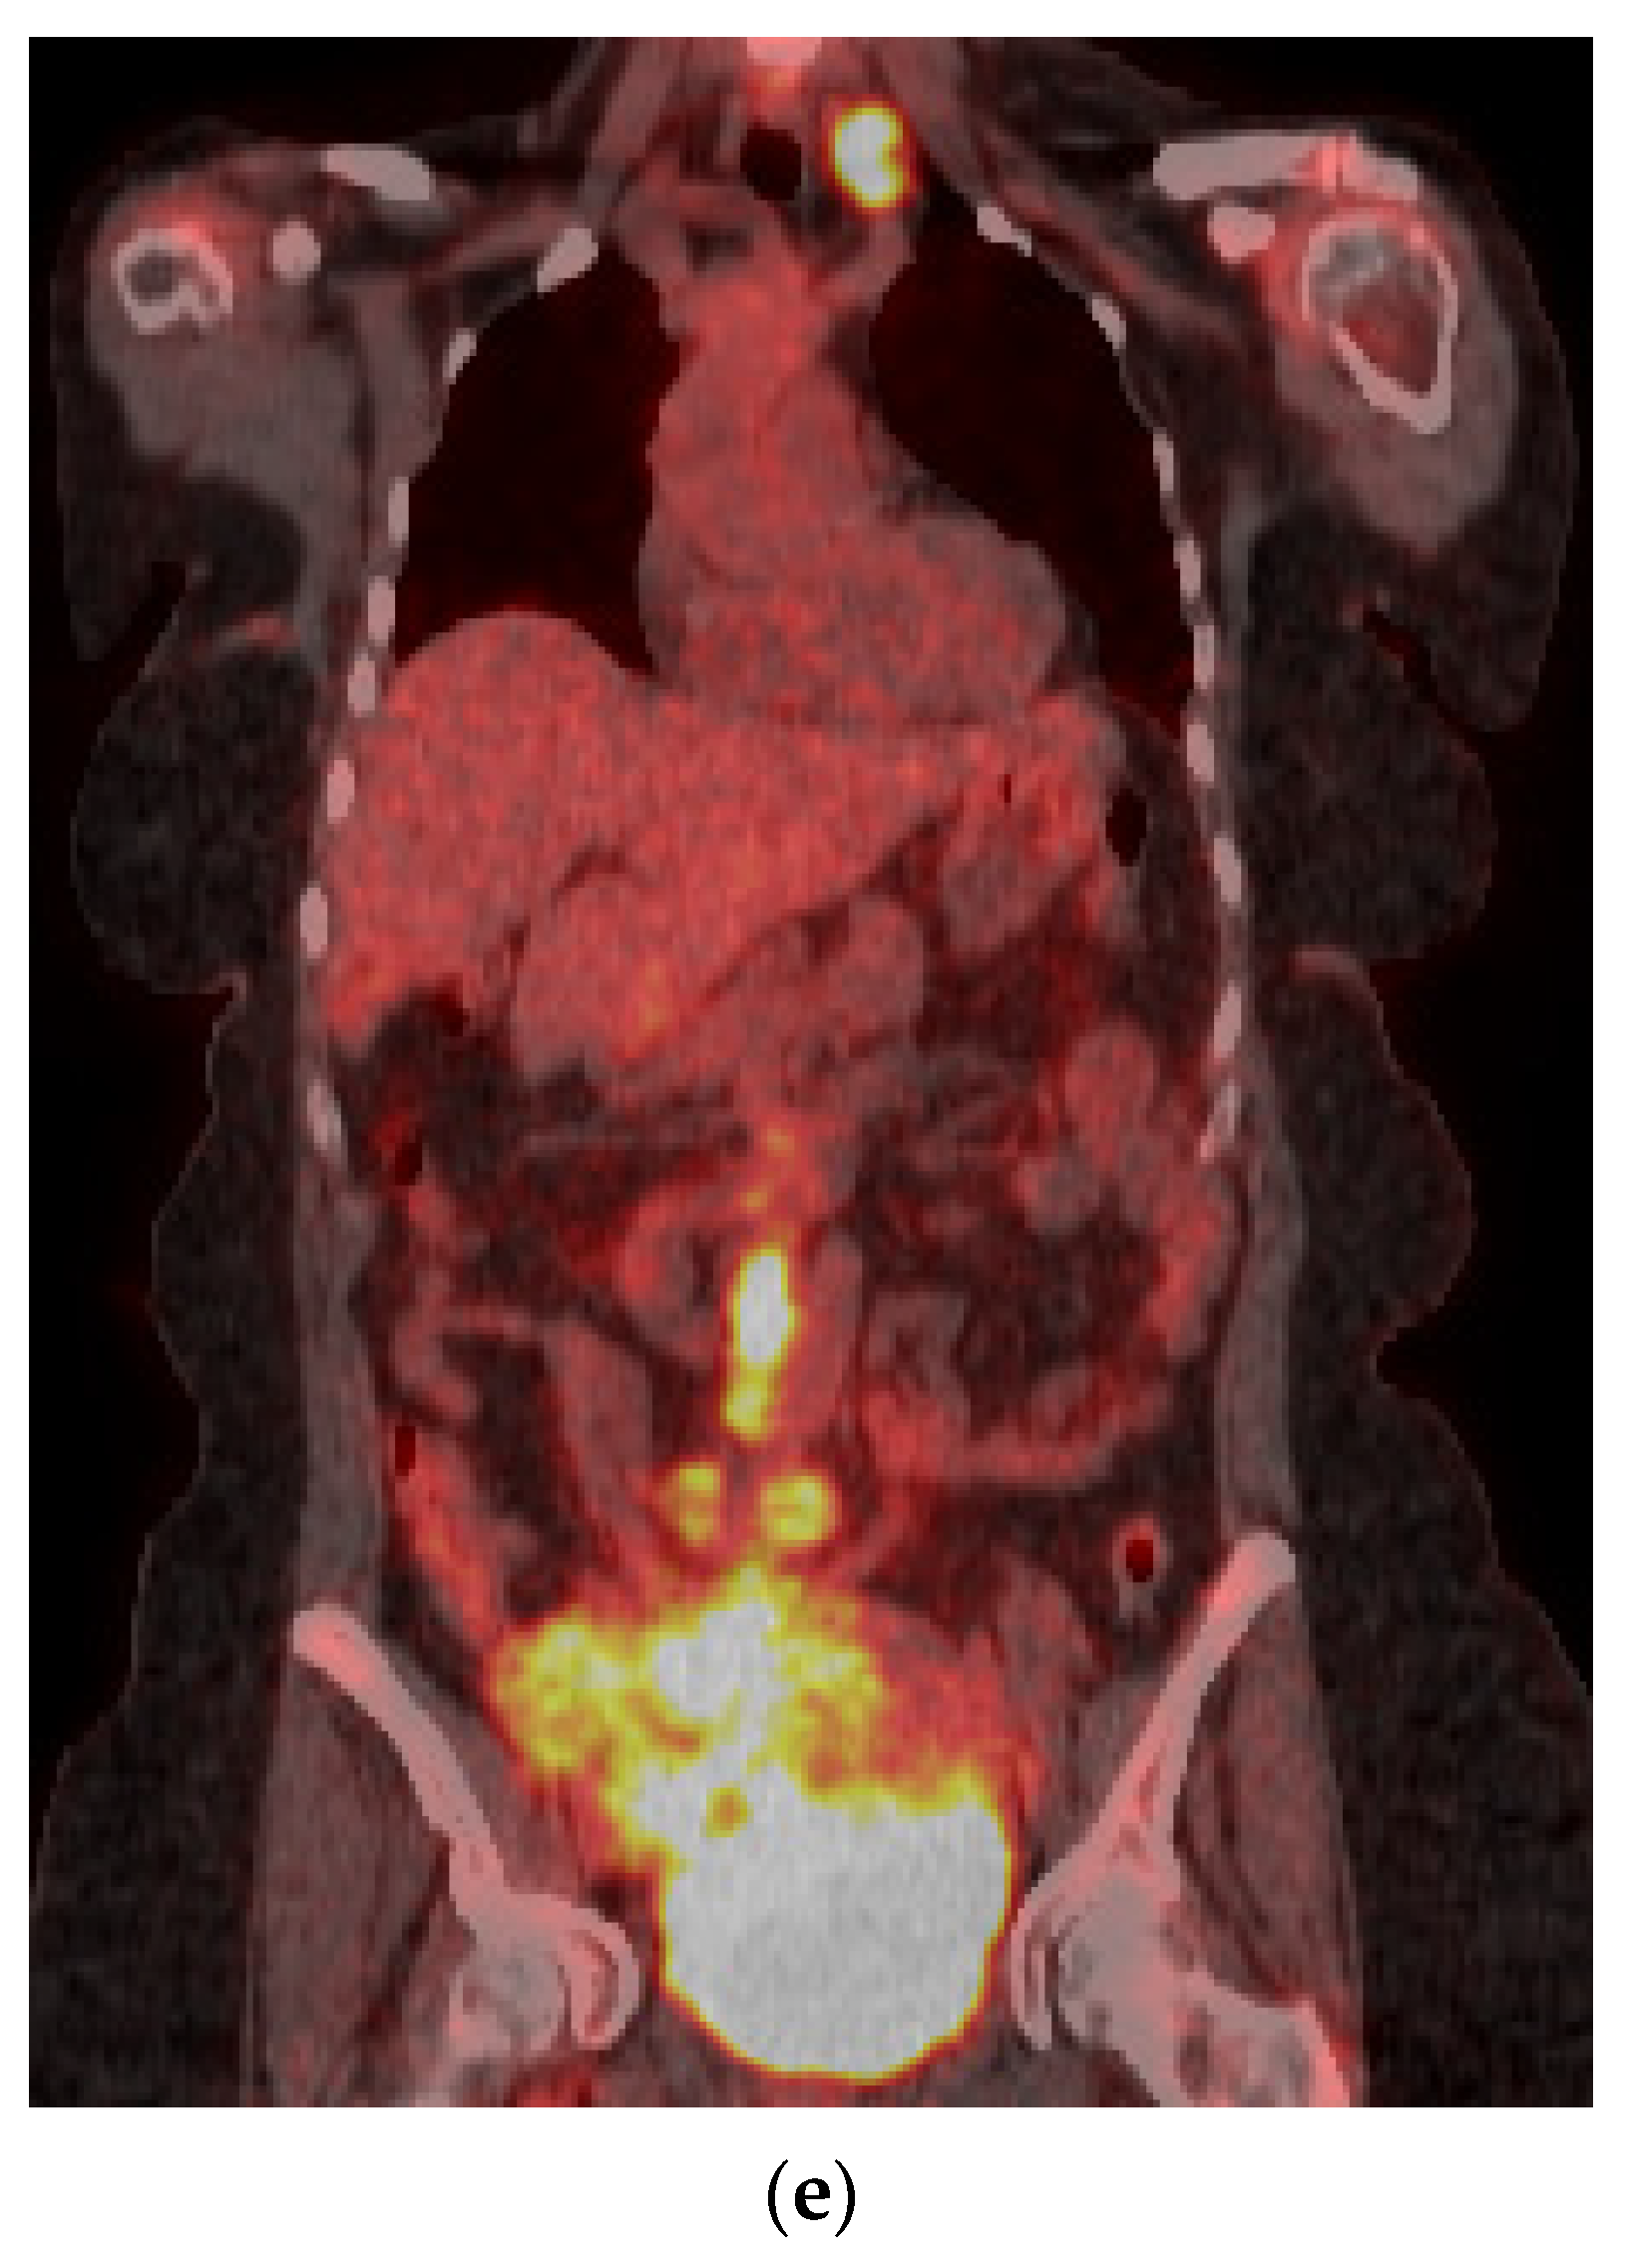

5.3. Positron Emission Tomography (PET)